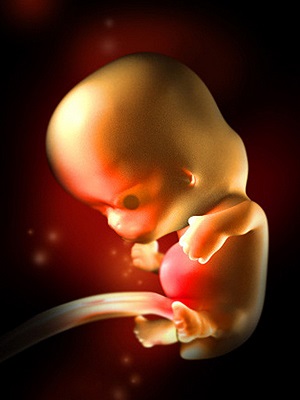

胚胎图

怀孕进入第7周了,这时的胚胎像一颗豆子,大约有13毫米长。现在如果你能看到自己的身体内部,你会发现胚胎已经有了一个与身体不成比例的大头。而且胚胎的面部器官十分明显,眼睛就像一个明显的黑点,鼻孔大开着,耳朵有些凹陷。

胚胎上伸出的幼芽将长成胳膊和腿,现在看上去已经很明显,手和脚看起来像小短桨一样。其它部分的成长包括垂体和肌肉纤维。现在你听不到胎心音,但是胚胎的心脏已经划分成左心房和右心室,并开始有规律的跳动,每分钟大约跳150下,比你心跳要快两倍。